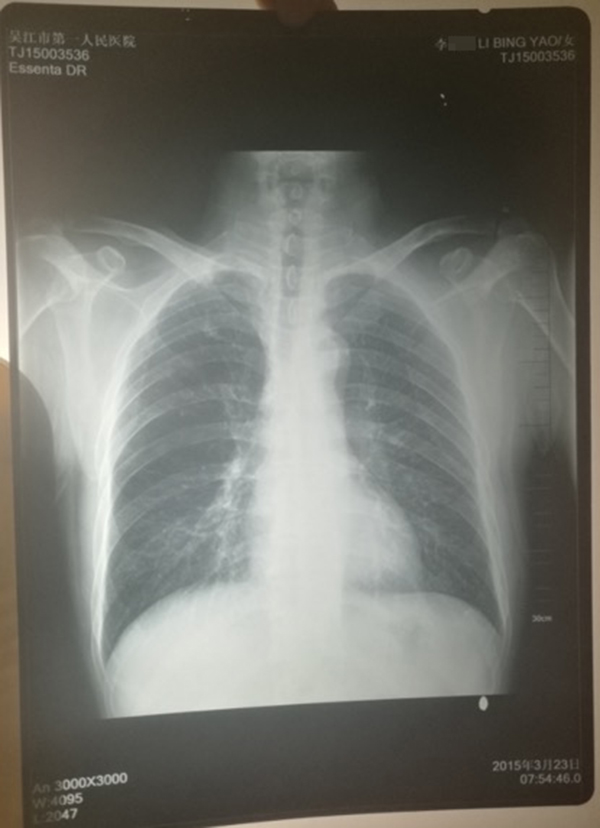

醫(yī)院提供的計(jì)建宏的“真實(shí)胸片”,寫有姓名“李某某”。 受訪人供圖

計(jì)云強(qiáng)稱,吳江區(qū)第一人民醫(yī)院曾提供一份印有“李某某”姓名的胸片,并稱該胸片才是計(jì)建宏的“真實(shí)影像結(jié)果”。

對(duì)于“李某某”姓名的胸片,上述吳姓主任稱,經(jīng)過醫(yī)院核查,兩份胸片的結(jié)果都是“正常”的,“如果結(jié)果是不一樣的話,那么問題就大了,但是因?yàn)槭且粯拥慕Y(jié)果,所以不能認(rèn)為是‘漏診’或‘誤診’。”

對(duì)于醫(yī)院的回應(yīng),計(jì)云強(qiáng)認(rèn)為醫(yī)院是將皮球踢給了患者,并對(duì)醫(yī)院解決事情的態(tài)度不滿,同時(shí)還對(duì)醫(yī)院提供的印有“李某某”姓名的父親胸片真實(shí)性存疑,“醫(yī)院應(yīng)該主動(dòng)去證實(shí)片子是我父親的。”